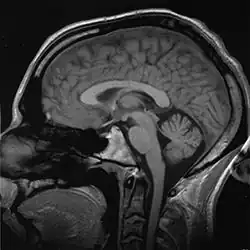

Imaging technologies are often essential to medical diagnosis, and are typically the most complex equipment found in a hospital including: fluoroscopy, magnetic resonance imaging (MRI), nuclear medicine, positron emission tomography (PET), PET-CT scans, projection radiography such as X-rays and CT scans, tomography, ultrasound, optical microscopy, and electron microscopy.